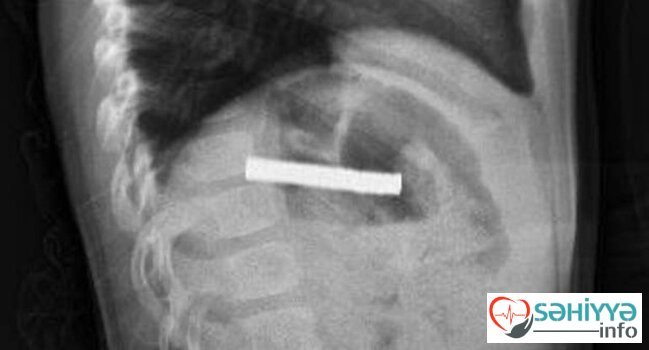

Fırat Universitetinin Uşaq Qastroenterologiyası, Hepatologiya və Qidalanma kafedrasının müdiri Prof.Dr.Yaşar Doğan endoskopik üsulla uşağın qida borusuna ilişib qalmış 19 maqniti çıxarıb.

Maqnitlər uzun müddət qida borusunda ilişib qalıb, yemək borusu və mədə girişində zədələr yaranıb.